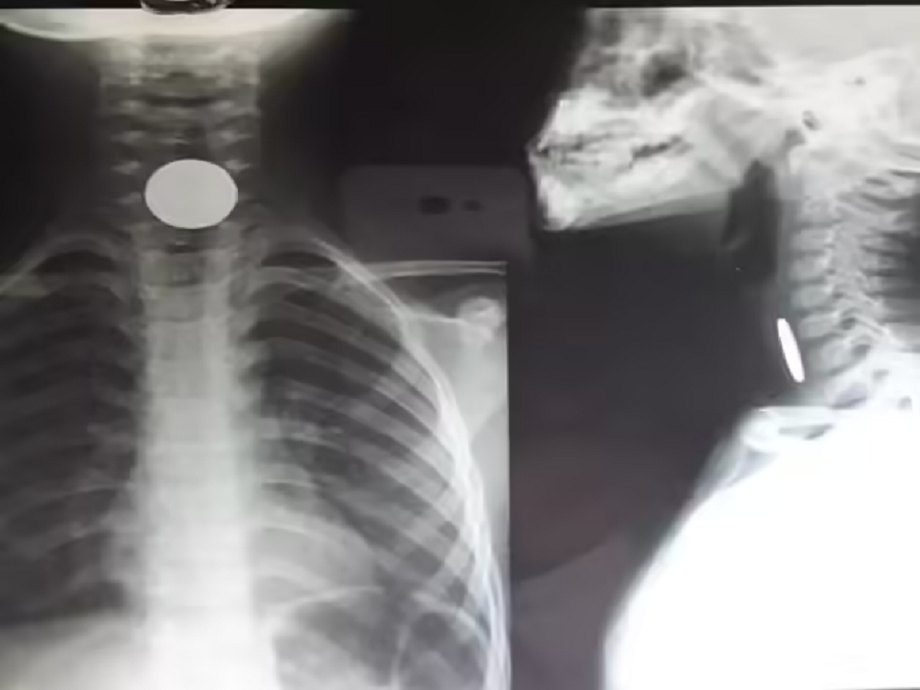

- Get an X-ray

- This will tell if the swallowed object is still in the stomach or not. In case of a harmless object, X-ray can be done even after 24 hours, because there is a higher chance of it reaching the stomach after a night's sleep.